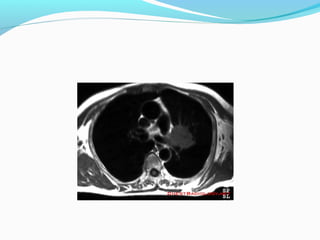

T4 - tumor

Invasion of vital mediastinal structures: fat, heart, trachea,

esophagus, great vessels, recurrent laryngeal nerve, carina.

Invasion of vertebral body.

Malignant pleural or pericardial effusion (cytologically

proven).

Separate tumour nodule(s) in a different ipsilateral lobe to

that of the primary tumor.